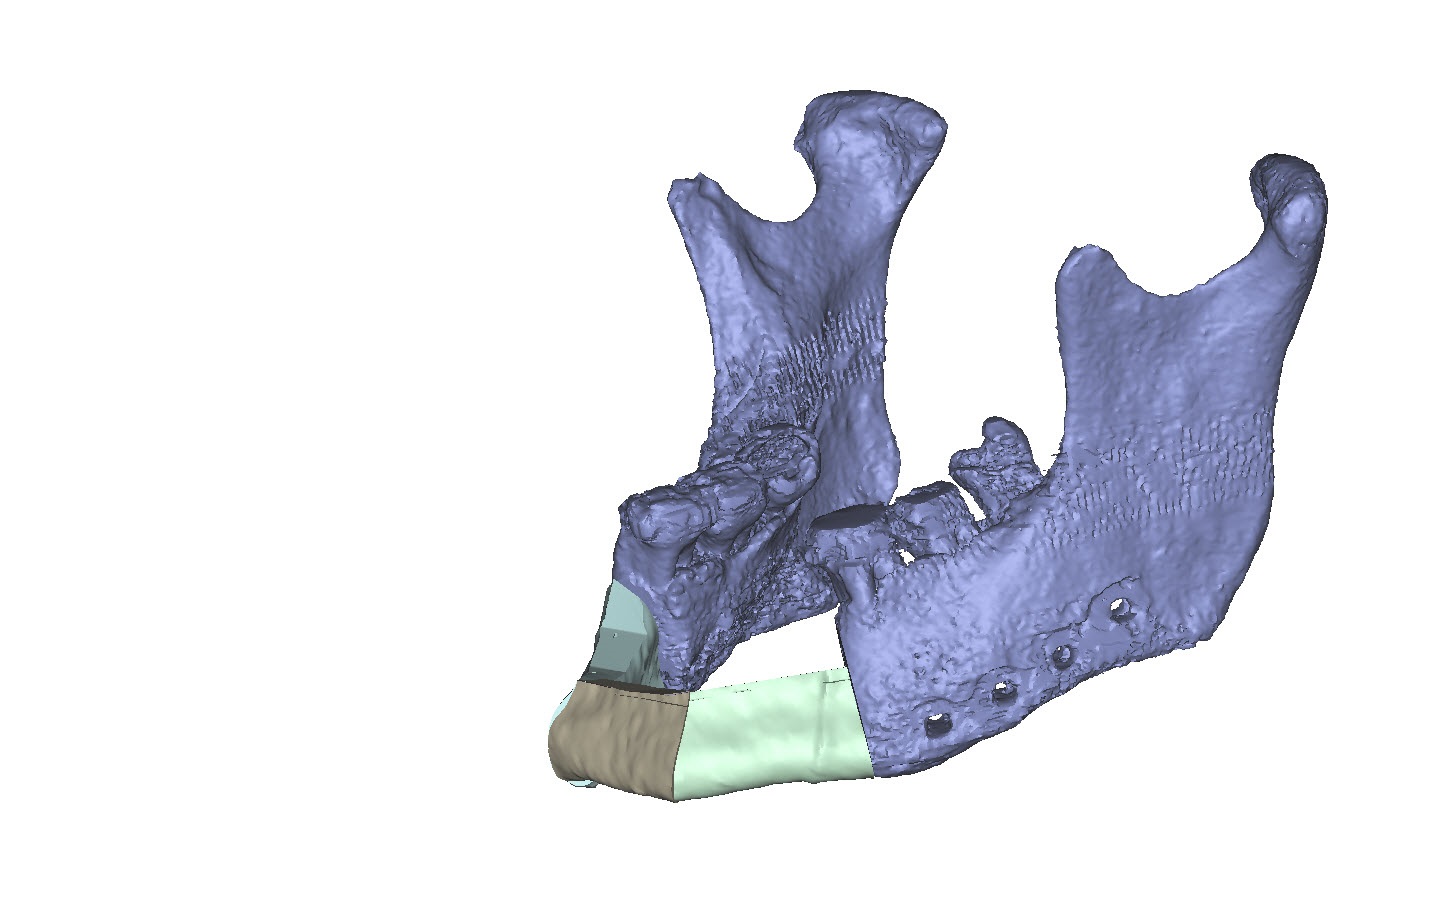

Computer-assisted planning (ProPlan CMF/TRUMATCH CMF Solutions) provides a virtual 3 dimensional model for a detailed osseous reconstruction of the maxilla or mandible with sub-segments of the lateral scapular border and/or tip (Fig. 1) based on high-resolution CT scans of the craniofacial skeleton and scapular region. To transfer such graphical representation accurately into real surgery requires an assorted toolkit of stereolithography (STL) models, selective laser sintered (SLS) templates for bone contouring and sub-segmentation osteotomies and patient specific implants (PSI).

A 58-year old male oncology patient required secondary mandibular reconstruction after composite resection of the floor of the mouth, mandibular symphysis, anterior body regions of the mandible and bilateral limited neck dissection. The existing reconstruction plate bridging the anterolateral mandibular defect was widely exposed through the intraoral mucosa. The chin and lower lip was sagging due to submandibular soft tissue shrinkage and lack of bone suspension. For secondary reconstruction, a two-in-one free flap from the subscapular vascular system containing the lateral scapular border and tip in combination with a latissimus dorsi flap was selected, since severe peripheral arterial occlusive disease prohibited the use of an osteofasciocutaneous fibula free flap. VSP was used to design the bony reconstruction with three sub-segments (total length 8.1 cm) from the right (nondominant arm) lateral scapular border and tip (Fig. 4).